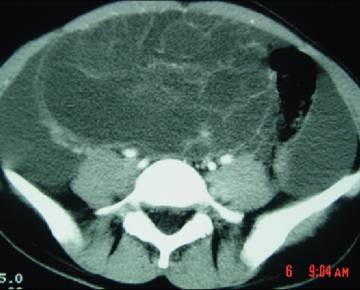

问题 40岁女性患者,下腹部隐痛、腹胀一年余,B超检查提示盆腔包块,行CT检查,如图,你认为最可能的答案是 ( )

选项 A、卵巢囊腺癌 B、卵巢浆液性囊腺瘤 C、卵巢囊肿 D、卵巢囊腺瘤 E、卵巢畸胎瘤

答案 D